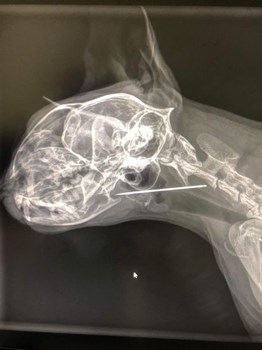

Se hele opslaget på RR Fliserens’ FacebooksideKatten Ella kom akut ind til vores vagtdyrlæge Line Kristensen . Hun havde pludselig skreget op og ejer kunne ikke finde ud af hvorfor 😿🐱 Ved undersøgelsen af Ella og hendes symptomer fik Line en ...

Se hele opslaget på Dyrehospitalet Heden ApS’ Facebookside